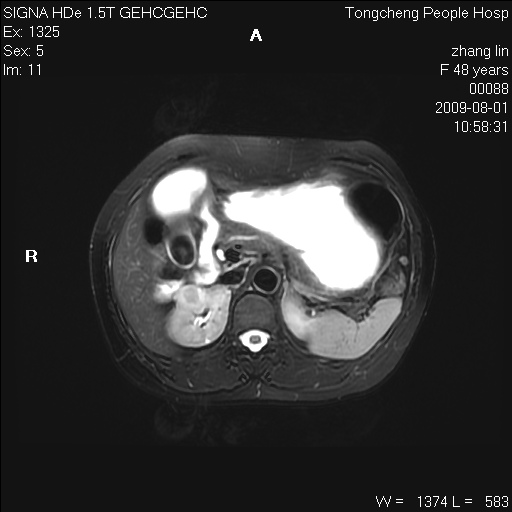

女,48岁。健康体检,彩超发现右肾占位性病变。平素健康。

临床诊断:右肾占位性病变,性质待定(囊肿?肿瘤?)。

上中腹部mr平扫+增强扫描,图像如下:

右肾上极见一类圆形病灶,t1wi呈等信号t2wi呈等高混杂信号,三期增强无强化,边界清---考虑囊肿出血。

同反相位均表现为等信号,病变无强化,考虑含蛋白的囊肿可能,弥散加权相或许有些帮助,